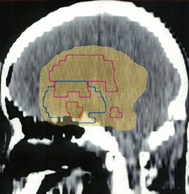

ここには,脳腫瘍の治療で良く用いられる(拡大)局所照射,全脳室系照射,全脳照射の治療計画と脳にあたる線量の分布を図にしてあります。実際に視床下部/下垂体にできた胚腫ジャーミノーマの患者さんに,25.2グレイを14回に分割してかける計画を立てた時のものです。上から順に局所照射,全脳室照射,全脳照射となっていますから,この照射がどのようなものかを理解する手がかりにしてください。青い線はCTV,黄色く塗ったのはPTVです。

全脳室照射

脳室すべて側脳室,第3脳室,第4脳室と下垂体に当てる照射です。胚腫ジェーミノーマでは最も汎用される照射方法です。(この図だとちょっと第4脳室の下の方が足りないかもしれません?)目的の場所には25.2グレイが入ります。同時に脳の60%くらいの容積に15グレイが入っています。この図では残念ながら,第4脳室の下端が外れてしまっています。